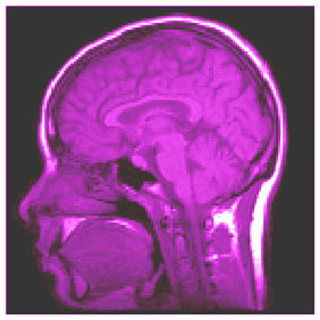

A brain scan image. (Image courtesy of David Cory.)